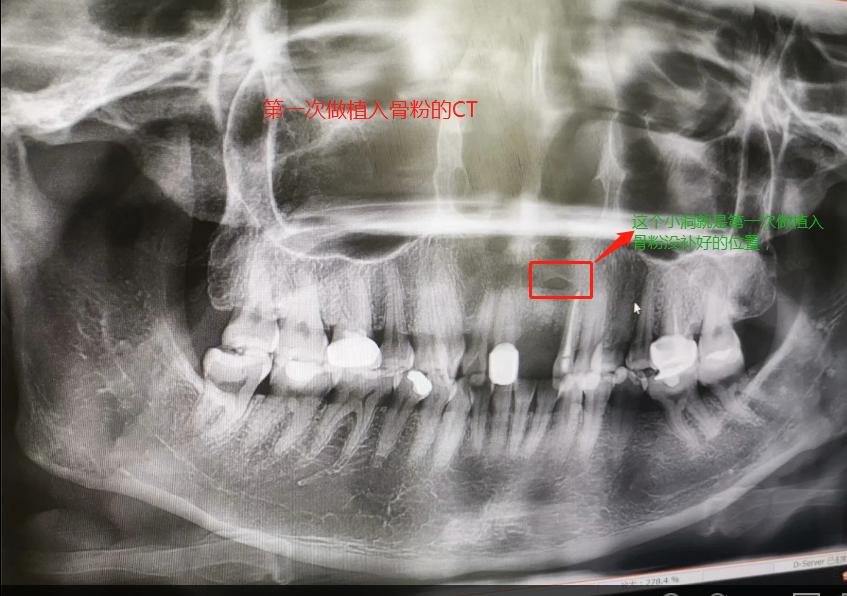

第一次做完植入手术后拍的CT

2019年7月27日做了种植骨粉手术,在医院要等半个小时留意一下是否有出血情况,没有就可以回家休息。做手术是自己一个人坐地铁来回的,勇敢吧。第一天嘴里都是血,第二第三天也是,脸也肿起来,也会有一点点骨粉掉出来,我那几天都是喝粥和喝汤,第四天才敢吃饭,第七天伤口就好了,可以带上临时假牙,因为我是上颚门牙,上颚骨头密度没有那么好,正常要等4个月左右,我的骨粉还是种植的,不是自身的骨头,所以必须要等半年才能种种植牙。等到2020年1月26日去种植牙根的时候,那个主任已经调去别的分店,第一次补完骨粉我就发觉里面还有个小洞,问医生里面为什么有个洞的,医生说没事的。我打算去分店种植牙齿的,以为跟我那个医生会比较了解我情况,后来那个的助理叫我不要去分店弄了,在这里安排个专家给我看。经过专家的诊断,我还有个洞没有补到骨粉,需要再做个补骨粉手术后等半年看看情况能不能种牙再说。我听了真想哭起来,大门牙好不容易空半年可以种牙了,结果还要我补骨粉,还要等那么长时间。经过跟这家医院医生沟通和别的门诊医生回答,决定还是回到这家医院做修复,跟助理谈了价格,他说就收取800元,补0.5克骨粉。于是就开始了第二次手术,第一次手术补了0.5克骨粉(2个单位,0.25克为一个单位),第二次补了0.75克骨粉,本来是0.5克骨粉,医生做手术的时候说还有点间隙,还需要0.25克骨粉,问我要不要加,我说加,就算要另外收费,我也要加,我的牙齿受的折磨太多了。我要好好弄好这颗牙齿,就收了800元,也没有额外收0.25克的骨粉钱。我在这家口腔医院花了6800元种植骨粉,第二次骨粉植入伤口比较大,医生说恢复期要12天,确实7天伤口还是没有恢复的很好。而且今年1月底爆发疫情,1月31日领导就让我们上班,我们公司是做医疗设备。伤口都没有完全康复就坚持上班了。